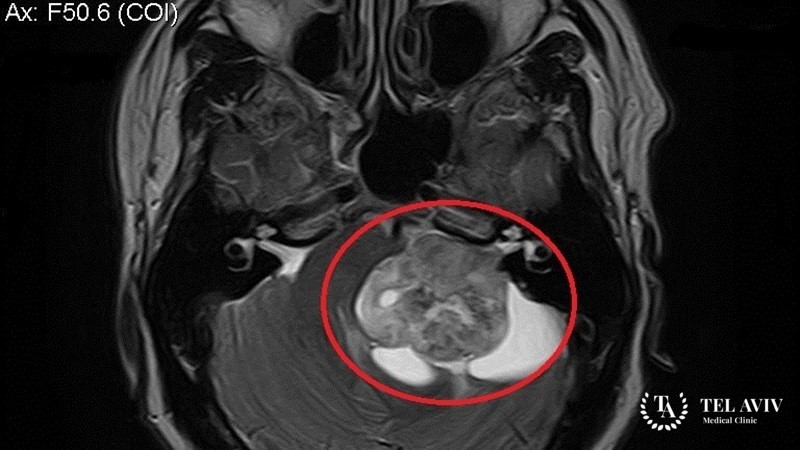

Шванномы обладают способностью к созданию миелиновой нервной оболочки. Это плотное новообразование, имеет неправильную, овальную форму, неровную поверхность с буграми. Опухоль покрывает соединительнотканная капсула.

Невриномы слуховых нервов признаны наиболее распространенными. Локализация патологий – мозжечковый, мостовой угол. Быстрые темпы сдавливания окружающих участков вызывают специфичную симптоматику: